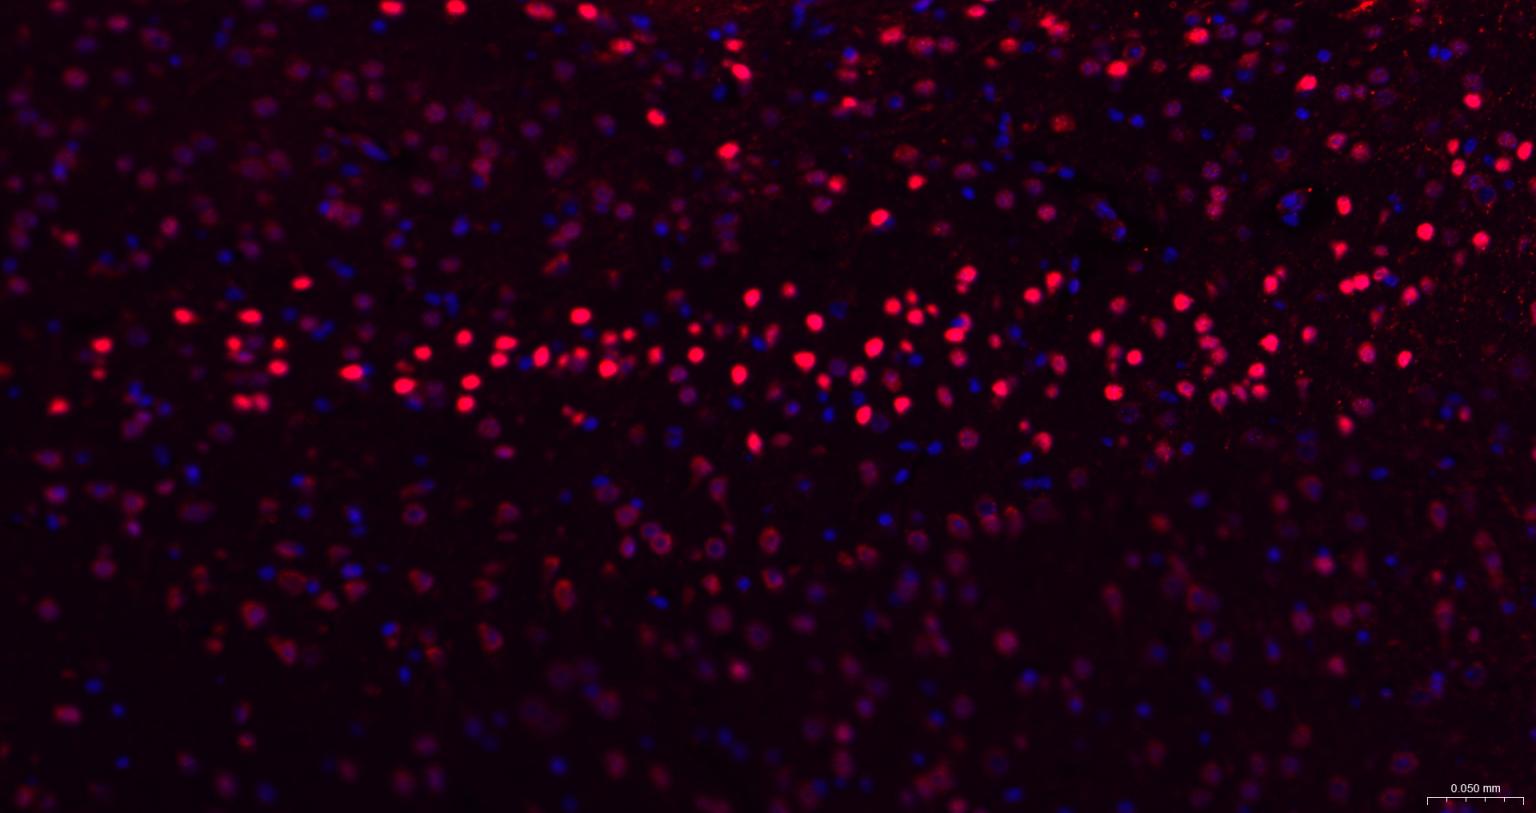

IHC-PHuman, Mouse, Rat1:100-500

IHC-FHuman, Mouse, Rat1:100-500

IFHuman, Mouse, Rat1:100-500

组织特异性

Brain.